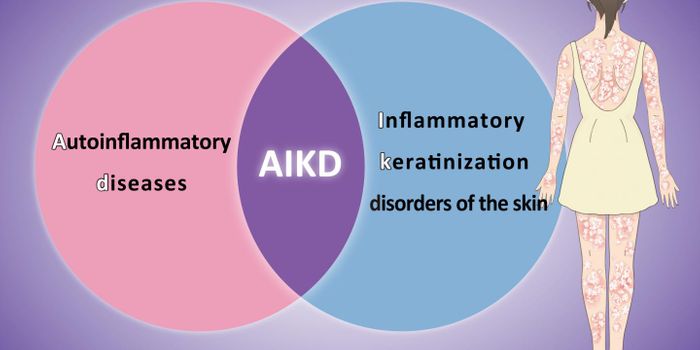

MAY 17, 2021ImmunologyInflammation, a process that was meant to defend our body from infection, has been found to contribute to a wide range o ...

MAR 18, 2020ImmunologyIn the words of C.S. Lewis, “Pain insists upon being attended to.” This is especially true for patients suff ...

FEB 06, 2017ImmunologyThe recent discovery of not just one, but multiple genes that fail to protect the gastrointestinal (GI) tract from infla ...